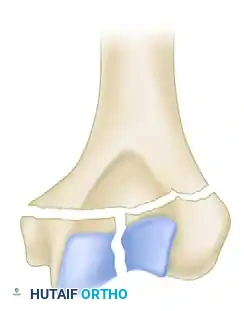

While the AO/OTA classification system is exhaustive (defining 61 types across A, B, and C categories), the Jupiter and Mehne classification, as well as the Mehne and Matta bicolumnar descriptions, offer superior utility for preoperative templating. Mehne and Matta categorize complex bicolumnar fractures based on their geometric configuration:

Mehne and Matta Low T-Fracture configuration.